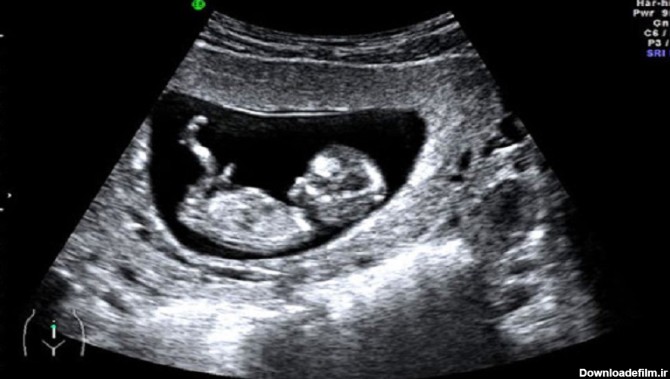

عکس جنین پسر و دختر در سونوگرافی

سونوگرافی در زمان های بارداری کاربردهای زیادی دارد و یکی از کاربردهای آن تعیین جنسیت جنین از روی تصاویر اسکن شده است.